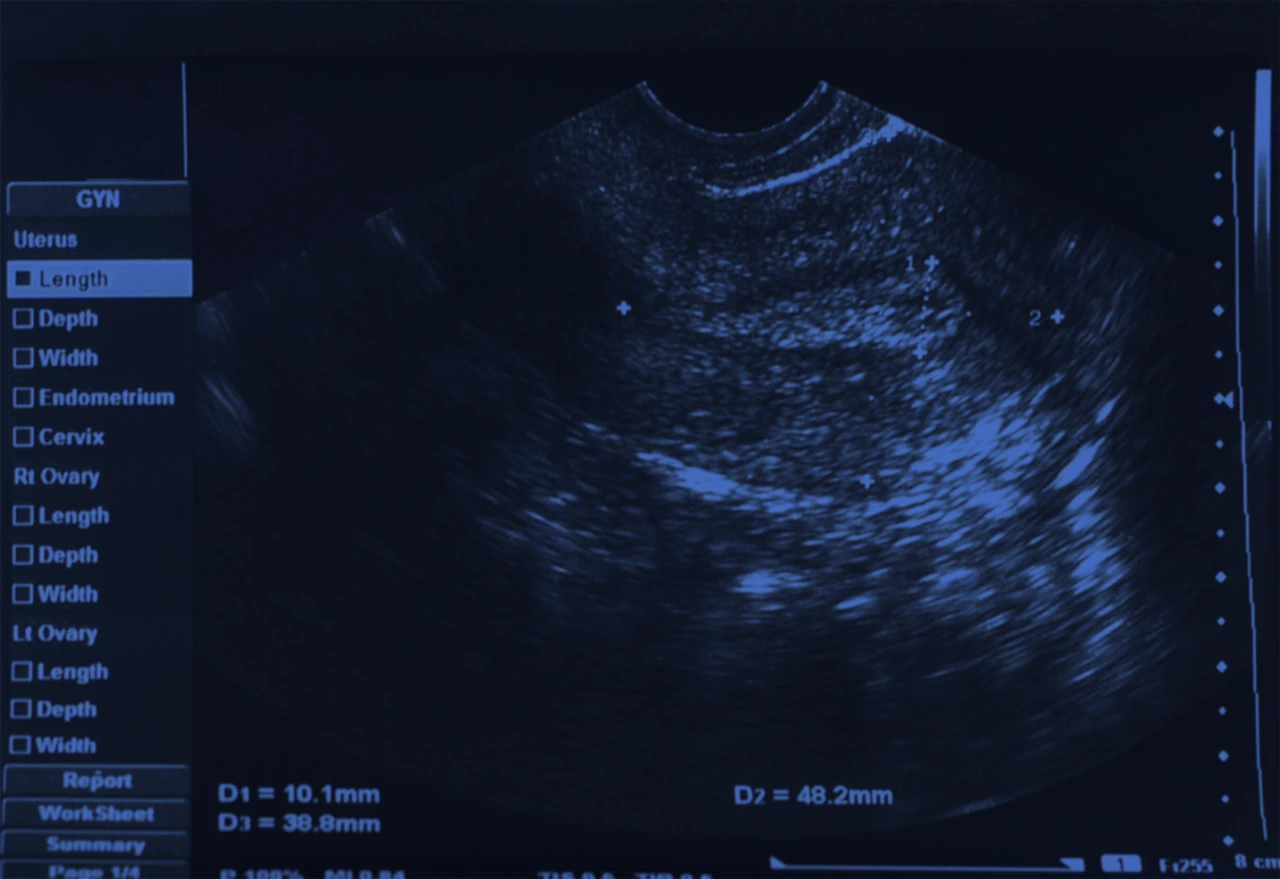

Ultrasonido pélvico como parte de los estudios diagnóstico de un tumor anexial.

Ecografía transvaginal o pélvica

Es el método más utilizado para identificar un tumor anexial, permite evaluar el tamaño, localización, bordes, contenido ya sea sólido, quístico o mixto; y la vascularidad.

La ecografía también ayuda a diferenciar entre un quiste funcional simple, un tumor de ovario benigno o una masa sospechosa de cáncer.